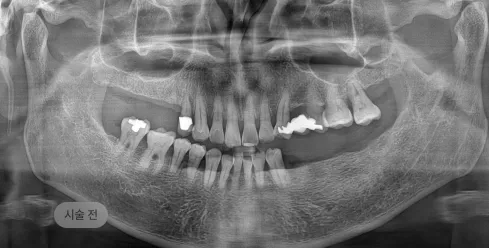

화면을 드래그하여 전/후를 비교해 보세요